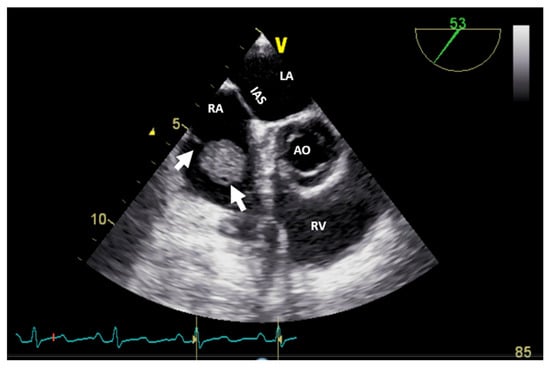

It can be used as a screening imaging method, but right heart tumors could be an incidental finding during a routine echocardiographic examination. This imaging technique is widely available (accessible), portable, and easy to perform, even at the patient’s bedside and in those who are hemodynamically unstable. It is safe, repeatable, cost-effective, and has a good spatial resolution (higher with TEE) and an excellent temporal resolution. For imaging small, highly mobile masses (<1 cm) or masses arising from valves, it is the optimal imaging modality [4]. TEE is more sensitive at identifying tumors smaller than 5 mm compared with TTE. Therefore, compared with TTE, TEE is better for the detection, location, and mobility of cardiac tumors and equivalent in the assessment of hemodynamic impact, compromising the compression/destruction/distortion of cardiac structures [12]. In some cases, the mass effect of a non-cardiac tumor severely compromises cardiac hemodynamics (Figure 1).

Figure 1.

Two-dimensional transthoracic echocardiography (apical 4-chamber view) with color Doppler showing external compression of the free right ventricular wall (arrow) in a patient with hepatomegaly due to a hepatic tumor, which explains hemodynamic instability (similar to a localized cardiac tamponade). AO, aorta; IAS, interatrial septum; LA, left atrium; LV, left ventricle; RA, right atrium; RV, right ventricle.